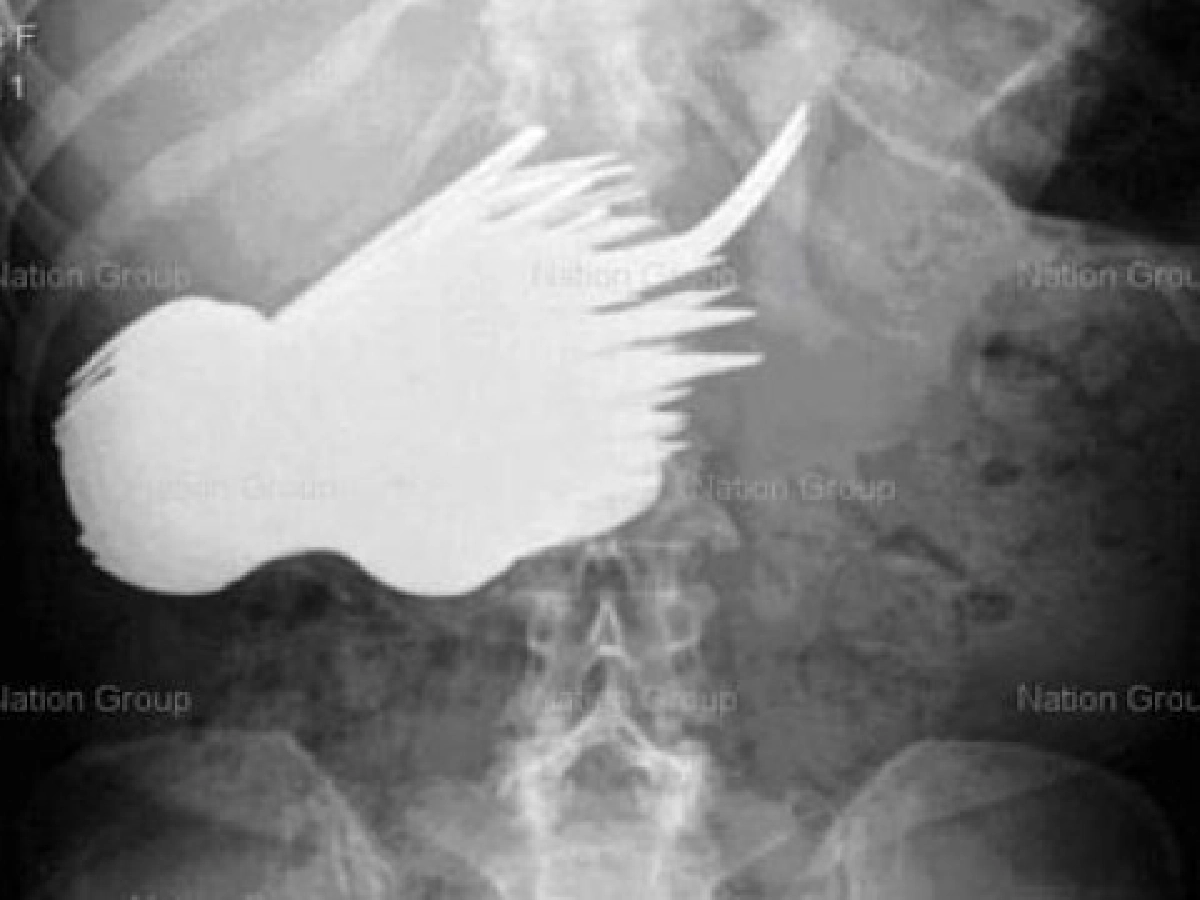

รายงานระบุว่า มาร์กาเร็ต วัย 52 ปี ไม่ได้ใส่ใจอาหารบนโต๊ะ แต่กลับรับประทานช้อนและส้อมอย่างหิวกระหาย และเธอต้องถูกนำตัวส่งโรงพยาบาลเพราะปวดท้อง ซึ่งภาพเอ็กซ์เรย์ได้แสดงให้เห็นสิ่งผิดปกติที่น่าประหลาด นั่นก็คือมีทั้งส้อมคันเล็กและช้อนชาอยู่ในท้องของเธอ และศัลยแพทย์ได้ผ่าเอาออกมาจนหมด